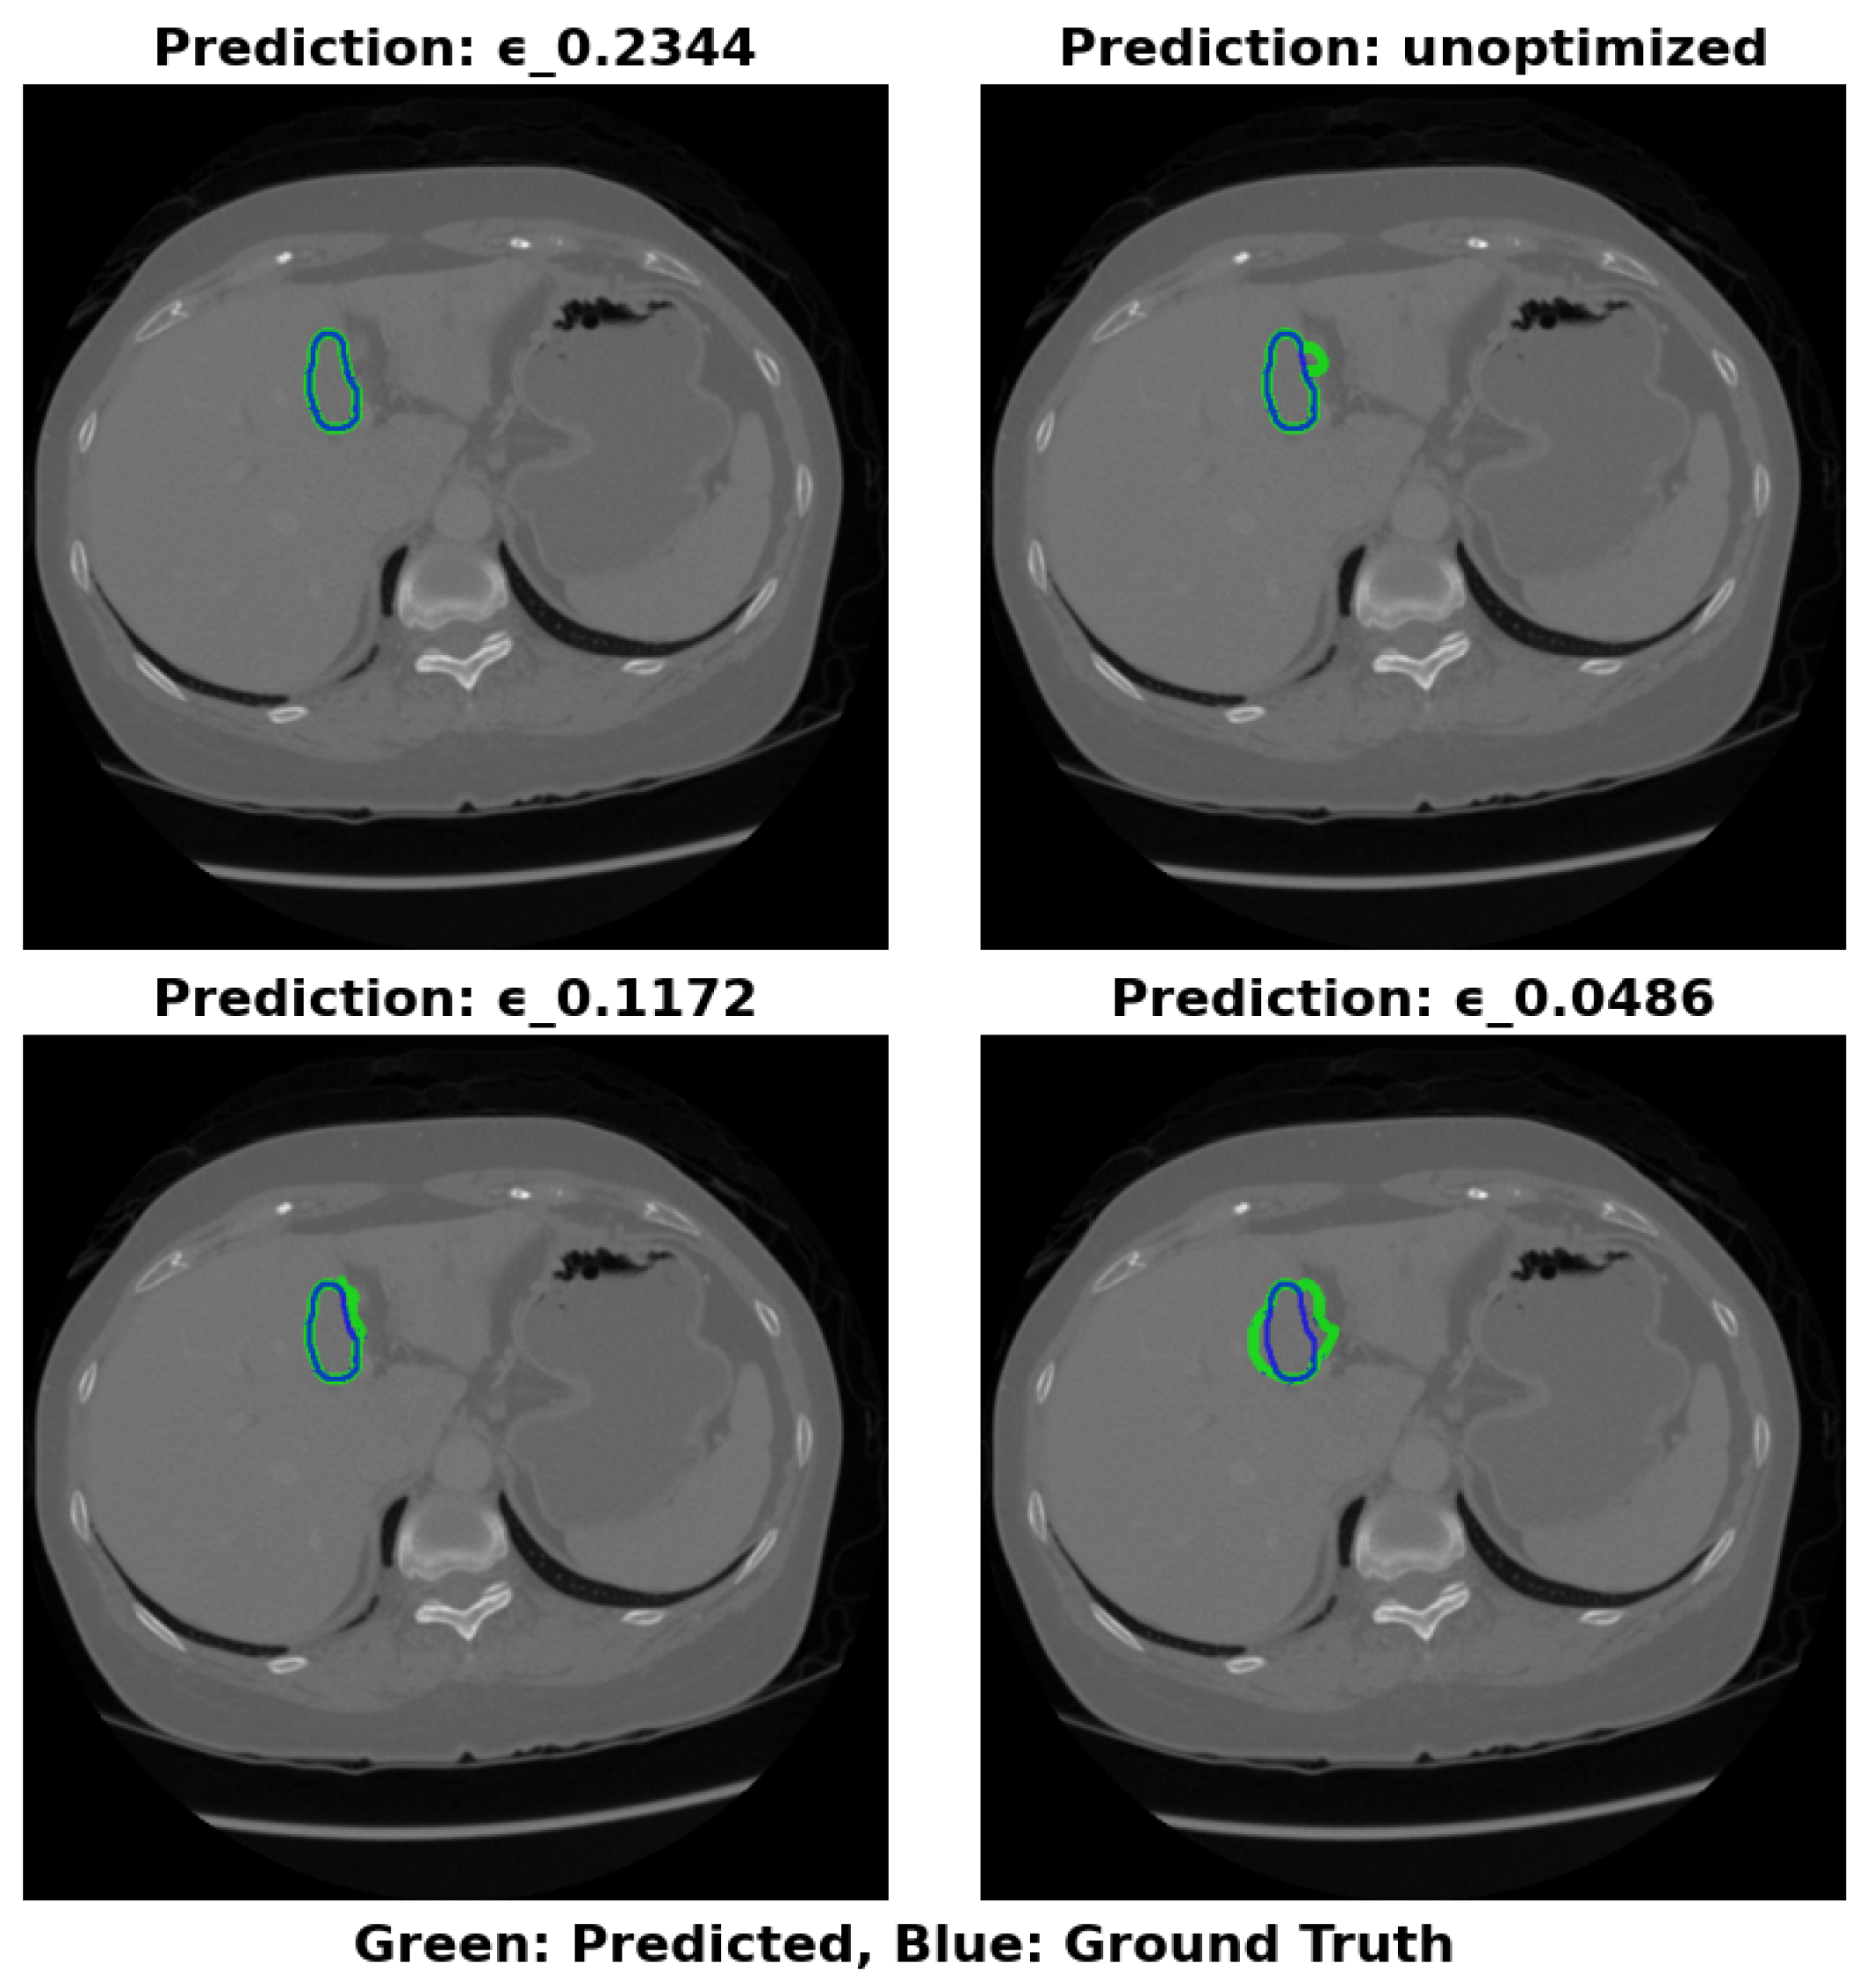

The visual segmentation results presented in Figure 4 support these findings. The configuration with ϵ =0.2344 exhibits the most accurate tumor boundary predictions, with minimal deviation from the true boundaries. In contrast, the unoptimized model, though effective, demonstrates less precise boundary delineation, particularly in complex tumor regions. These visual results confirm the quantitative findings, reinforcing that optimizing ϵ significantly enhances segmentation accuracy and computational efficiency.

Figure 4. Visual Results of Segmentation with Different ϵ Values on IRCADe 3D Dataset.

Preprints 150963 g004